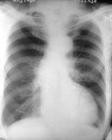

高血壓性心臟病是由於血壓長期升高使左心室負荷逐漸加重,左心室因代償而逐漸肥厚和擴張而形成的器質性心臟病。高血壓性心臟病一般出現在高血壓病起病數年至十餘年後,根據心功能變化情況可分為心功能代償期和心功能失代償期。在心功能代償期,病人可無明顯自覺症狀,但在心功能失代償期,則逐漸出現左心衰竭的症狀,開始時僅在勞累、飽食或說話過多時感心悸、氣喘、咳嗽,以後症狀逐漸加重,上述症狀呈陣發性發作,多表現為夜間陣發性呼吸困難並痰中帶血,嚴重時可發生急性肺水腫。

在超聲心動圖檢查方面,可見主動脈擴張,左右心室壁肥厚和各心腔擴大;發生心力衰竭時,可見心肌運動減弱,二尖瓣、三尖瓣及主動脈辨有舒張期返流,射血分數減低等。